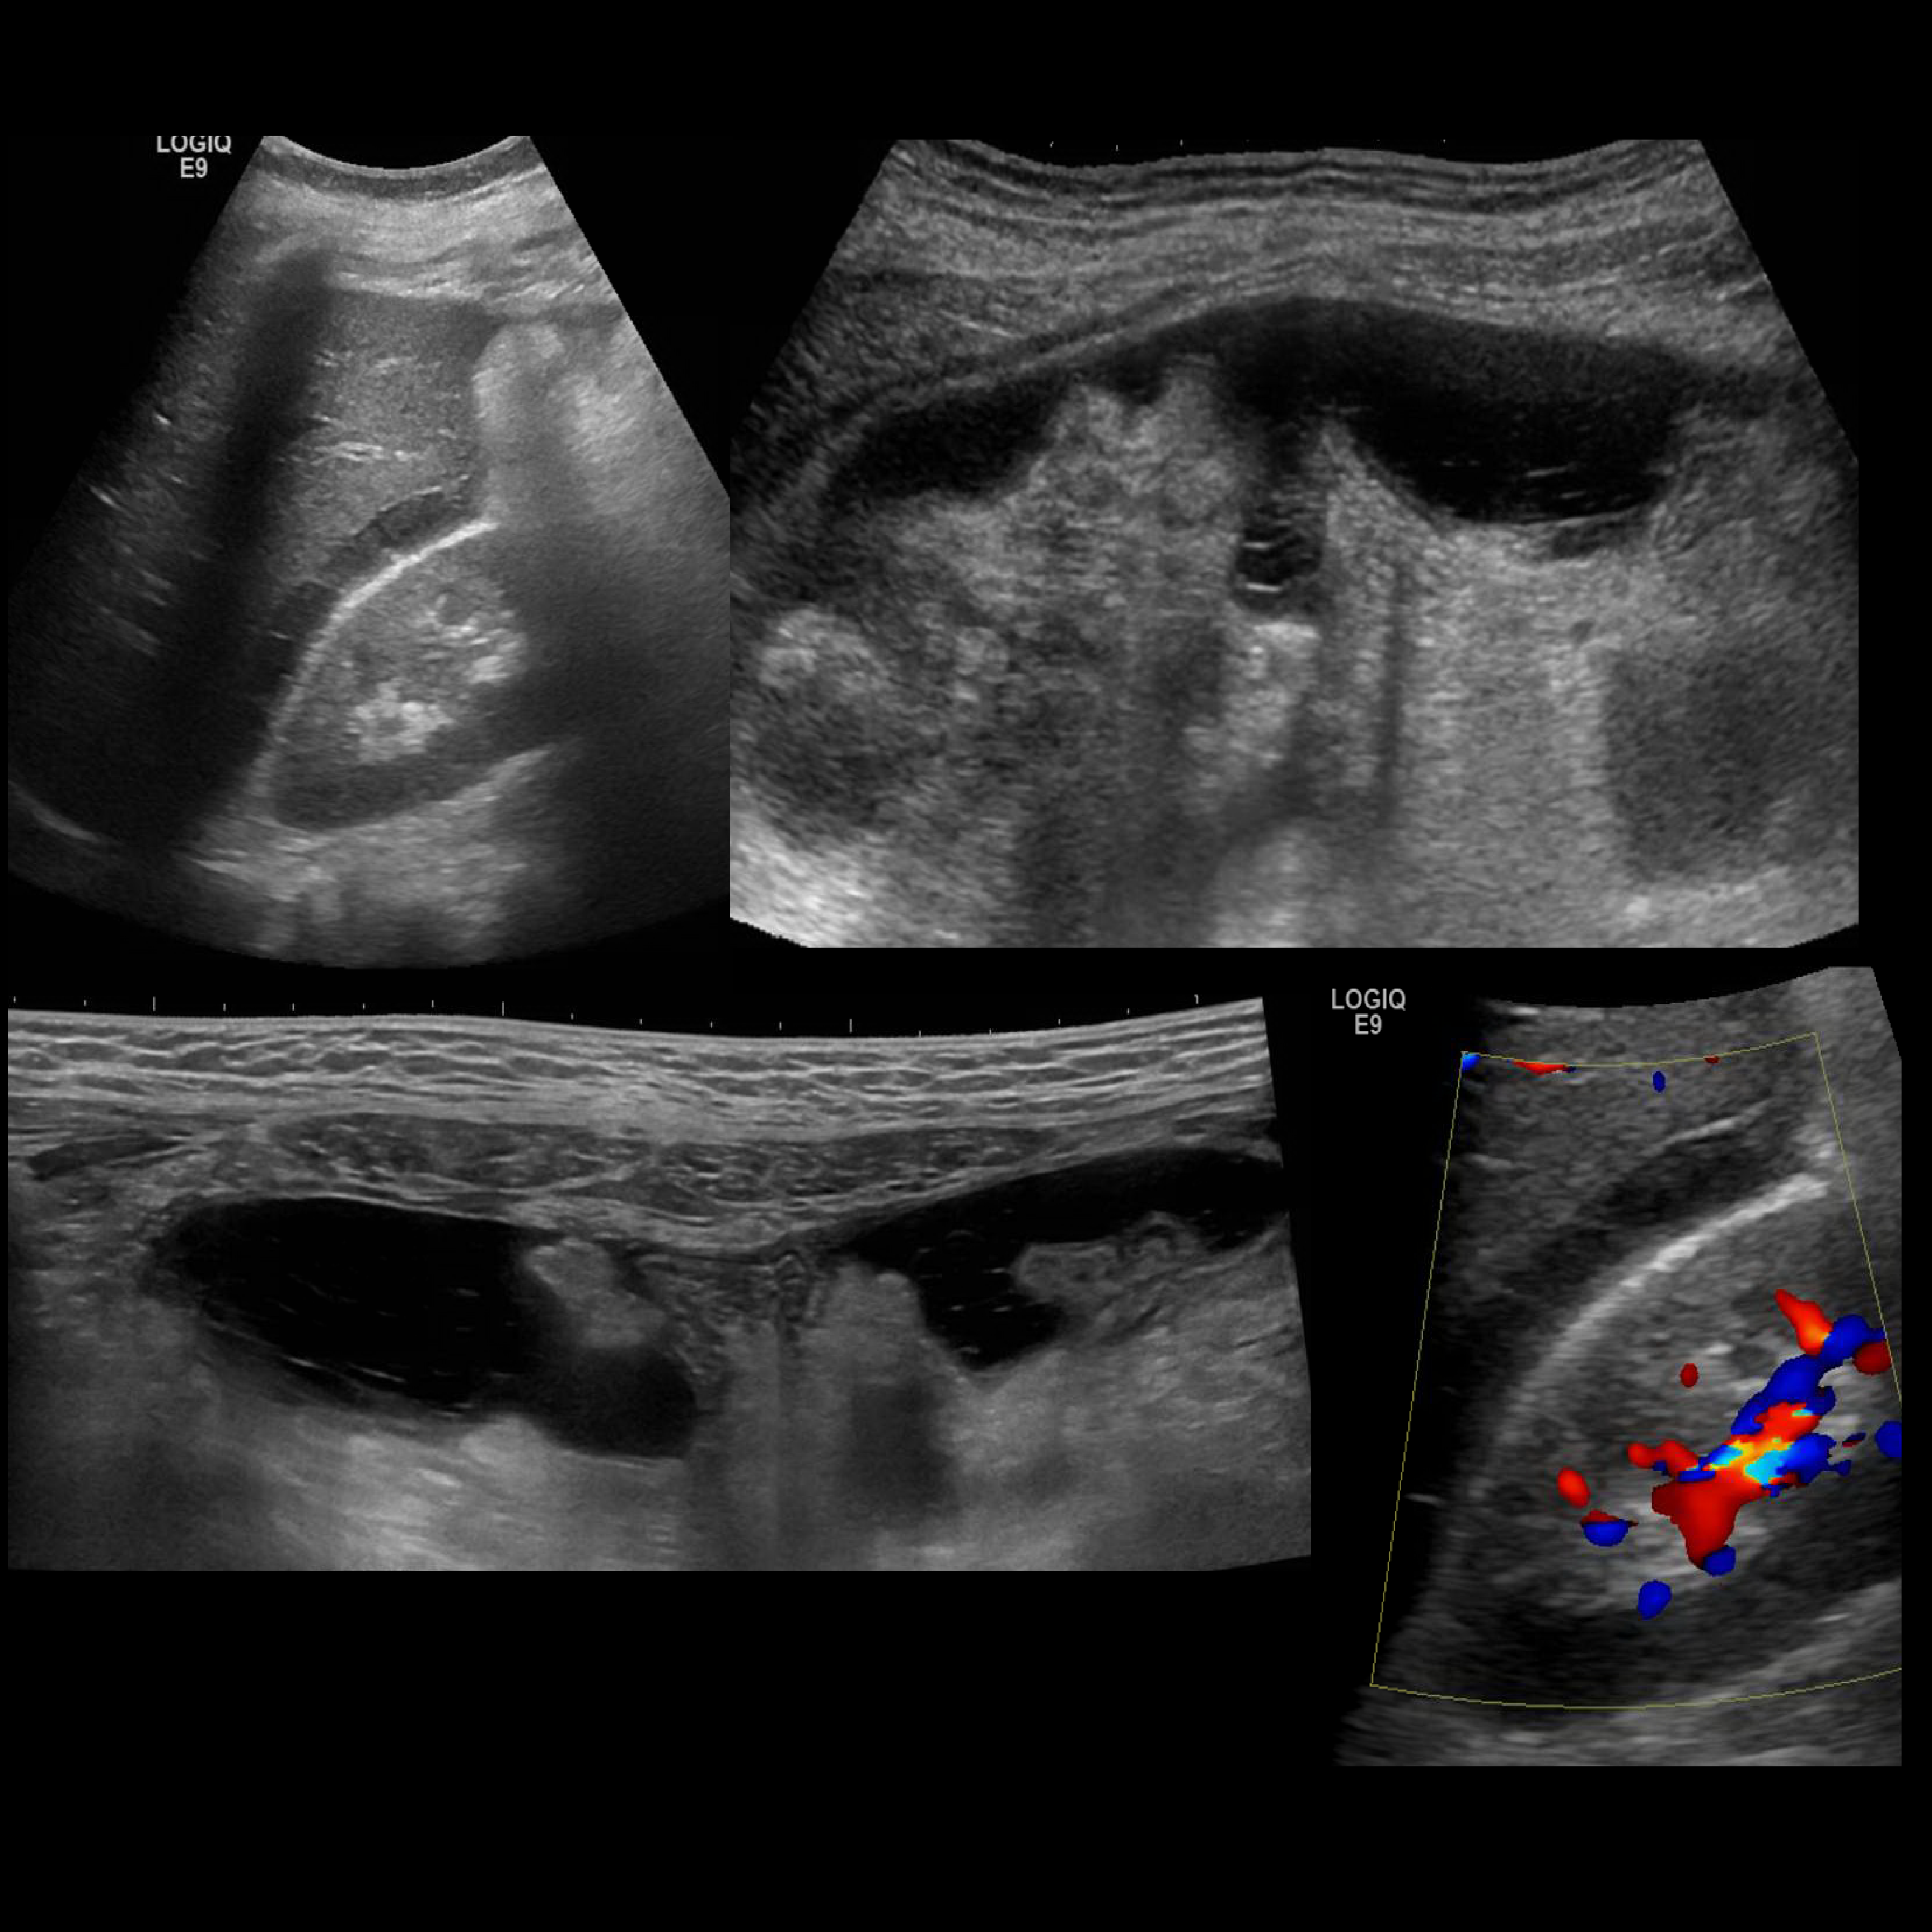

Appendicitis 7

Appendicitis found with hyperemia, free fluid and mural gas found to be perforated on surgery.